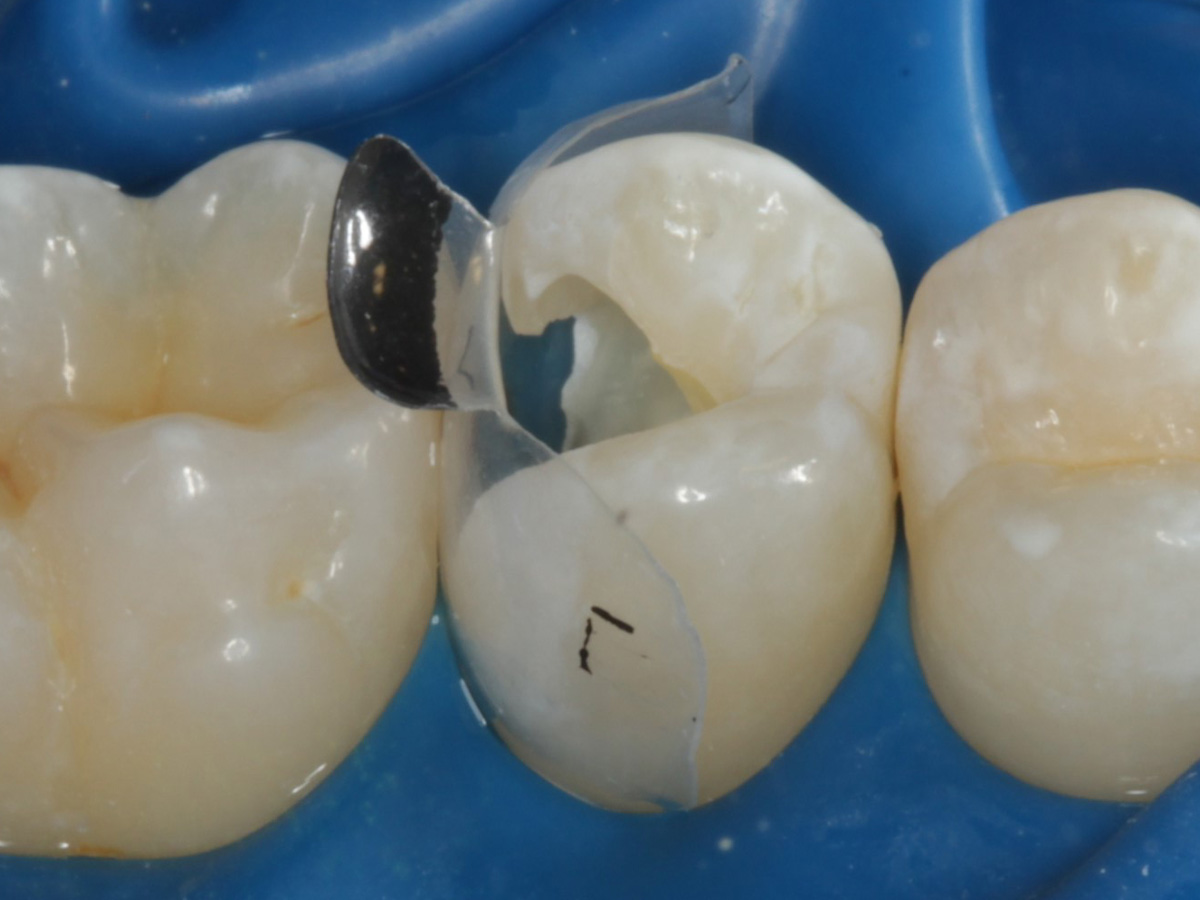

Abbildung 4

Schutz des Nachbarzahnes und des Kofferdams mit wiederverwandter Bioclear Biofit Matrize (gereinigt und sterilisiert)